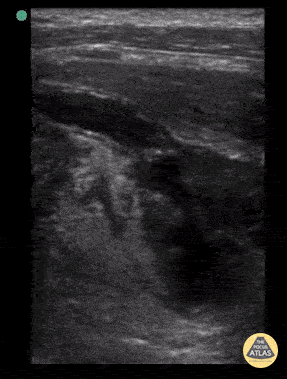

6y female with 2d abd pain, fever, nauesea, dysuria. OSH WBC 17.5, pyuria. Long axis view of the appendix draping down into the pelvis. Note how the regular bowel wall architecture is progressively obliterated as the appendix tracks distally into the pelvis, ending in full perforation with early abscess formation and surrounding hyperechoic fat. Contributor: Matthew Moake, MD PhD